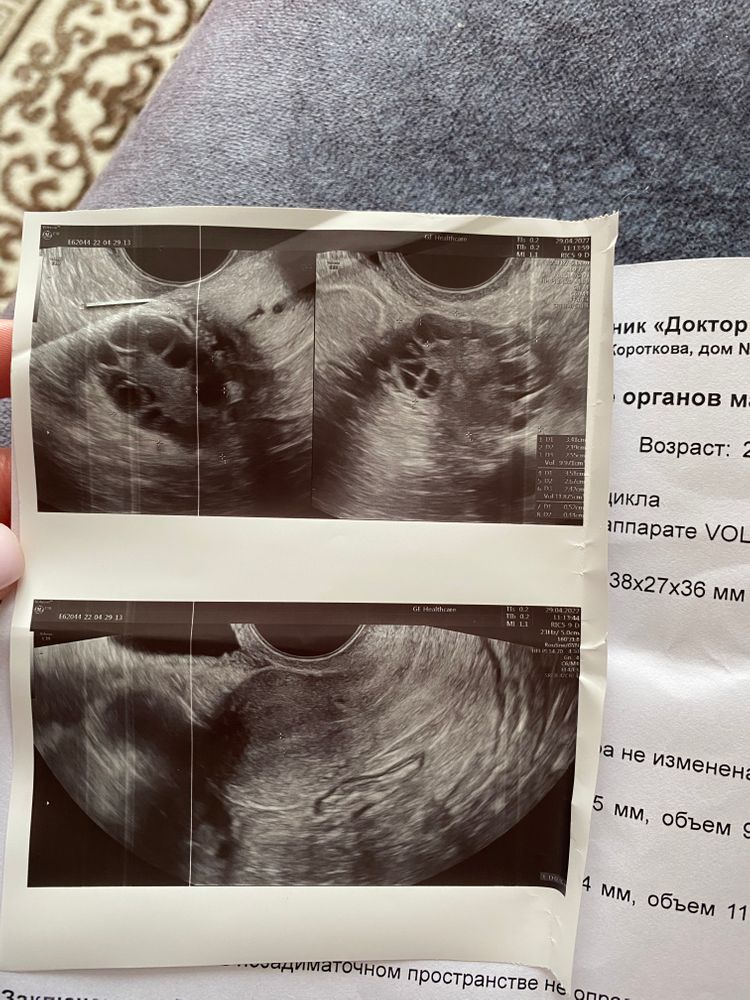

Планирую начать пить Клостилбегит, месячных нет , сегодня 70 день цикла, прошлые мес вызывали дюфастоном, сегодня была на узи, врач не говорит вызывать месячные а сразу начать приём клоста, прикладываю узи и хочу спросить ваше мнение нужно ли вызывать месячные при таких показателях, а уже после начать пить Клостилбегит, может кому-либо тоже так назначали стимуляцию?

Добрый день, по картинке узи СПКЯ , фолликулы расположены по границе ожерельем. Вы сдавали какие нибудь анализы? Если не сдавали, может сдадите ЛГ, ФСГ, Эстрадиол, пролактин и АМГ. Хотя бы будет видно хотя бы что -то. Сдавали тестостерон? Почему такая задержка созревания? Инсулинорезистентность проверяли?